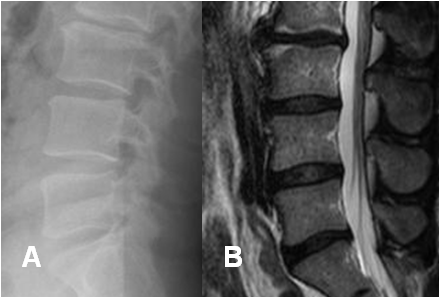

Fig 182. Espasmo muscular.

A: Rx lateral y B: RM sagital en T2. Rectificación por espasmo muscular.